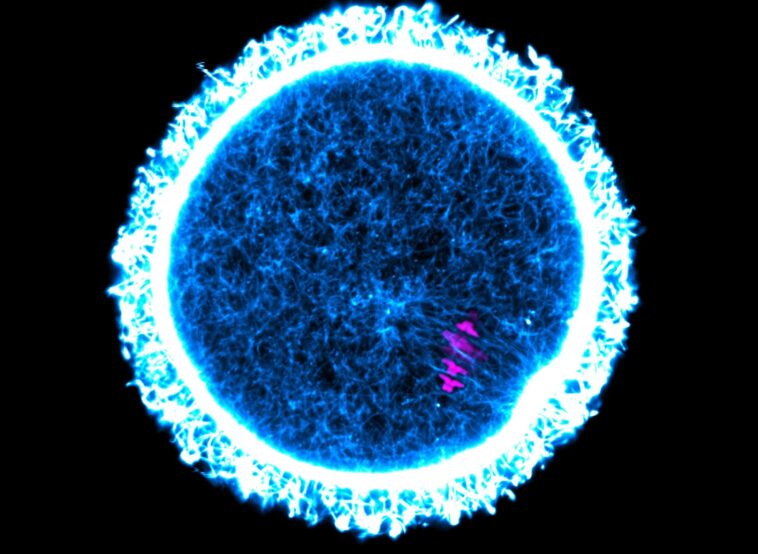

Les femelles mammifères naissent avec tous les ovules qu’elles auront jamais dans leurs ovaires. Certaines de ces cellules vivent donc longtemps et doivent rester fonctionnelles pendant toute cette période. Des expériences sur des souris ont maintenant montré que des protéines à très longue durée de vie dans l’ovaire peuvent maintenir les ovules en bonne santé et préserver la fertilité pendant longtemps. Dans l’ovule de souris présenté ici, les chromosomes sont colorés en magenta et la protéine cytosquelettique actine est colorée en bleu et blanc. Crédit : Melina Schuh / Institut Max Planck des sciences multidisciplinaires